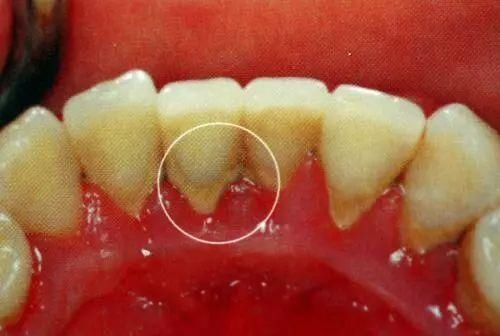

大块牙结石快要脱落,为什么牙齿也松动了?

明明牙结石要脱落了,怎么感觉牙齿摇摇欲坠?

牙结石自己也能掉落吗?当然了,一般牙结石是不会轻易自行脱落的,牙结石导致的牙龈炎或者牙周炎,也还是

牙结石掉了一块怎么办?因为牙结石对我们可不怎么友好,一般不会「自行脱落」,一般的刷牙也很难清除,最后

牙结石是很多口腔疾病的万恶之源,有些人认为牙结石会自己掉落不需要治疗牙结石自动脱落是别想啦,重视起来

而且特别难闻,怪不得口臭会这么重,一大块牙结石什么时候才能掉完?正常来说,牙结石几乎不会脱落,只